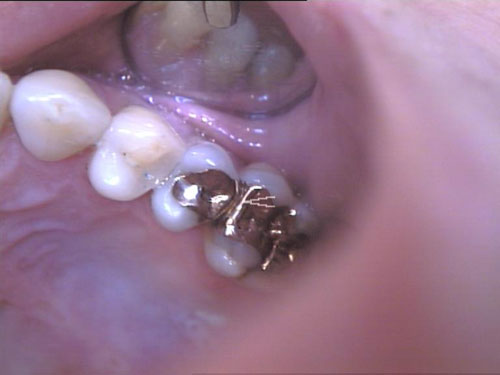

Goldinlay